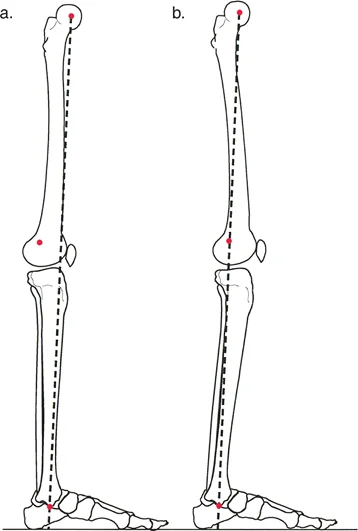

المحور الميكانيكي للطرف السفلي

المحور الميكانيكي للطرف السفلي هو خط الجاذبية الذي ينقل قوة رد فعل الأرض أثناء مرحلة الوقوف والمشي. يُعرف أيضًا باسم "خط ميكوليتش" (Mikulicz Line).

• خط ميكوليتش: هو خط يُرسم من مركز رأس عظم الفخذ إلى مركز مفصل الكاحل (السطح المفصلي لعظم الساق). في الطرف الطبيعي والمحاذي بشكل صحيح، يمر هذا الخط إلى الناحية الإنسية قليلاً من مركز مفصل الركبة (تحديدًا عبر الشوكة الظنبوبية الإنسية).

• انحراف المحور الميكانيكي (MAD): إذا وقع خط ميكوليتش إلى الناحية الإنسية (الداخل) من مركز الركبة، فإن الطرف يُعتبر في وضعية "تقوس للداخل" (Varus). وإذا وقع إلى الناحية الوحشية (الخارج)، فإن الطرف يُعتبر في وضعية "تقوس للخارج" (Valgus). المسافة من مركز الركبة إلى هذا الخط تُحدد مدى الانحراف. هذا الانحراف هو المؤشر الرئيسي على توزيع الوزن غير المتساوي على مفصل الركبة، مما يُؤدي إلى خشونة مبكرة.

المحور التشريحي للعظم

المحور التشريحي هو الخط الذي يمر بمنتصف جسم العظم (الديّافيز).

• في عظم الساق (الظنبوب): يكون المحور التشريحي والمحور الميكانيكي متوازيين تقريبًا (عادةً ما يكون الفرق 0-2 درجات).

• في عظم الفخذ: ينحرف المحور التشريحي عن المحور الميكانيكي بحوالي 7 درجات (يتراوح من 5 إلى 9 درجات اعتمادًا على عرض الحوض وطول الفخذ).

زوايا توجيه المفاصل

إن استعادة المحور الميكانيكي ليست سوى نصف المعركة؛ يجب أيضًا أن تكون المفاصل موجهة بشكل موازٍ للأرض لمنع قوى القص (Shear forces) التي تُسبب تآكلًا إضافيًا. نقيس هذه الزوايا باستخدام تقاطع المحاور التشريحية أو الميكانيكية مع خطوط المفاصل:

• الزاوية الوحشية السفلية لعظم الفخذ (mLDFA): الطبيعي 85°–90° (المتوسط 87°).

• الزاوية الإنسية العلوية لعظم الساق (MPTA): الطبيعي 85°–90° (المتوسط 87°).

• الزاوية الوحشية العلوية لعظم الفخذ (LPFA): الطبيعي 90°.

• الزاوية الوحشية السفلية لعظم الساق (LDTA): الطبيعي 86°–92° (المتوسط 89°).

يُعد فهم هذه الزوايا ضروريًا للجراح لتحديد مكان التشوه بدقة وتخطيط التصحيح اللازم لاستعادة الوظيفة الطبيعية للمفصل.